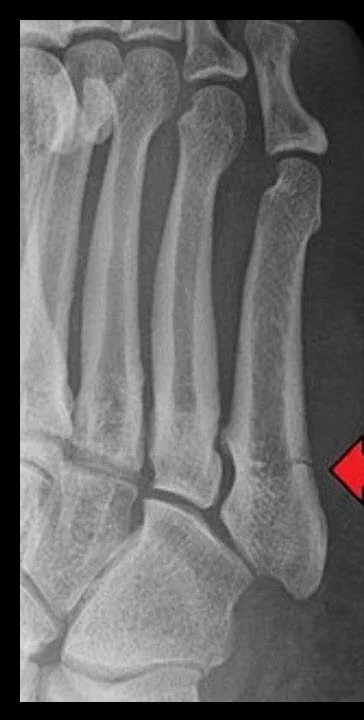

Imaging is used to confirm the diagnosis. X-rays typically identify the fracture location and allow classification into zones, which is critical for guiding treatment. Follow-up imaging may be obtained to assess healing progress.

Zone I fractures occur at the tuberosity of the fifth metatarsal and are often referred to as avulsion fractures. These injuries typically result from an inversion ankle injury and generally have a good blood supply, allowing them to heal reliably with non-surgical treatment.

Zone II fractures, commonly known as Jones fractures, occur at the metaphyseal-diaphyseal junction of the bone. This area has a relatively limited blood supply, which increases the risk of delayed healing or nonunion. These fractures require closer monitoring and may warrant surgical treatment in active individuals.

Zone III fractures occur farther along the shaft of the bone and are often associated with stress injuries or repetitive loading. These fractures carry the highest risk of delayed healing and nonunion and frequently require surgical intervention, particularly in athletes or patients with persistent symptoms.

Accurate identification of the fracture zone is essential, as it directly influences treatment recommendations, recovery time, and long-term outcomes.